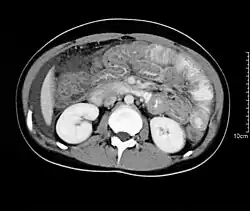

Hypereosinophilia, the hallmark of allergic response, may be absent in up to 20% of patients, but hypoalbuminaemia and other abnormalities suggestive of malabsorption may be present. CT scans may show nodular and irregular thickening of the folds in the distal stomach and proximal small bowel, but these findings can also be present in other conditions like Crohn's disease and lymphoma.